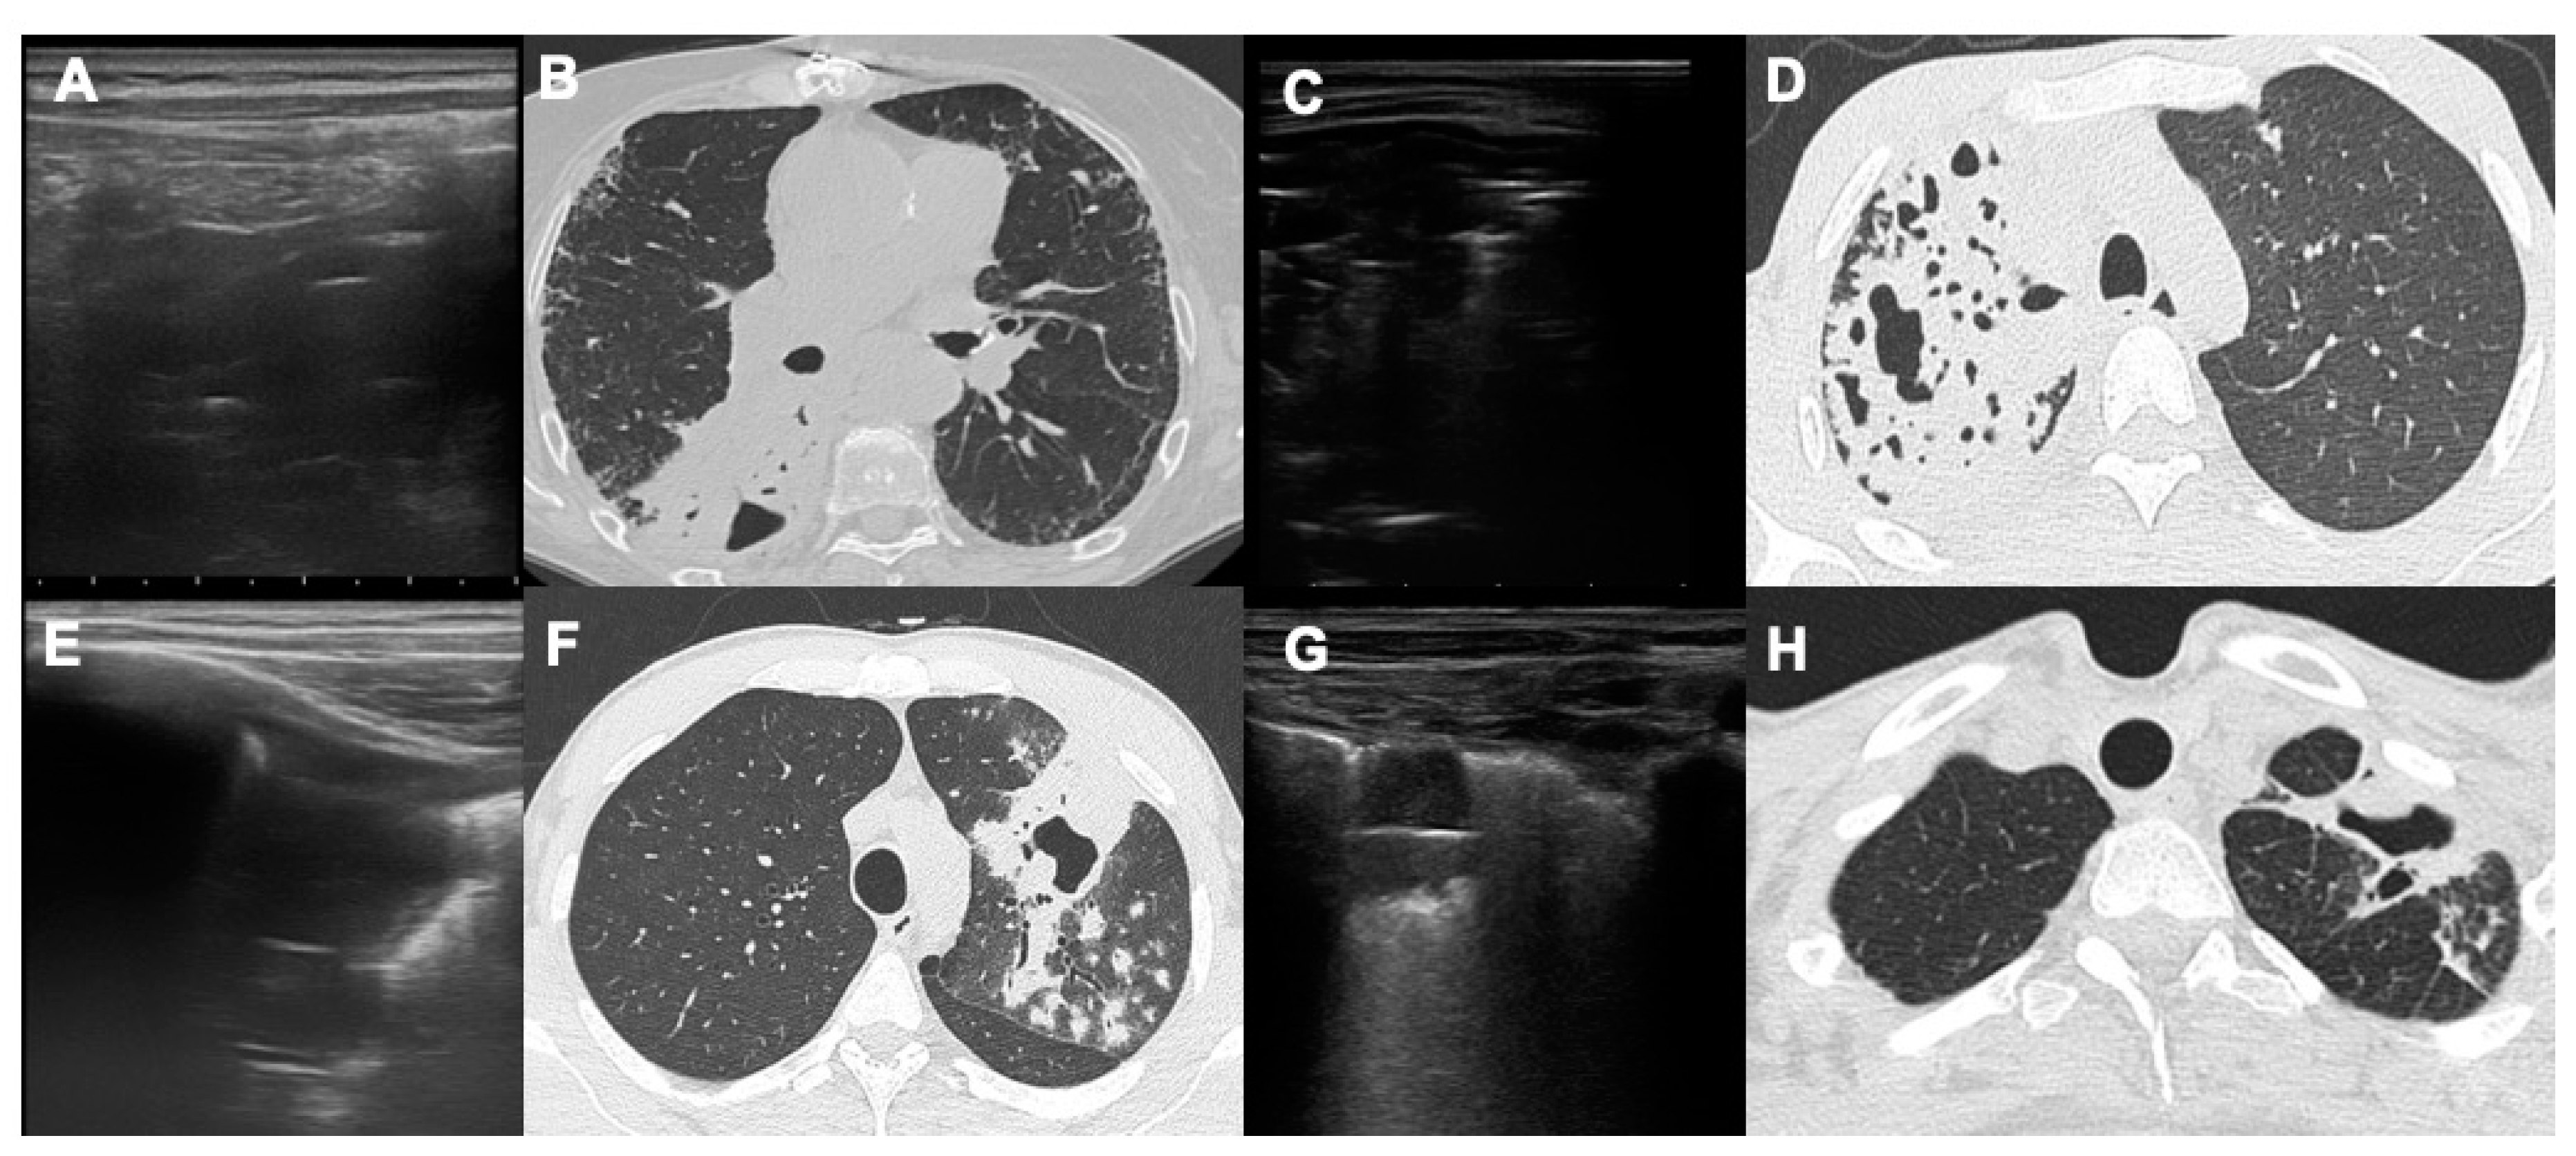

- Giannelli F, Cozzi D, Cavigli E et al. Lung ultrasound (LUS) in pulmonary tuberculosis: correlation with chest CT and X-ray findings. J Ultrasound 2022, 25(3):625-634. [CrossRef]

- Montuori M, Casella F, Casazza G et al. Lung ultrasonography in pulmonary tuberculosis: a pilot study on diagnostic accuracy in a high-risk population. Eur J Intern Med 2019 66:29–34. [CrossRef]

| Lung Ultrasound | 11/58 (19%) | 4/24 (16.7%) |